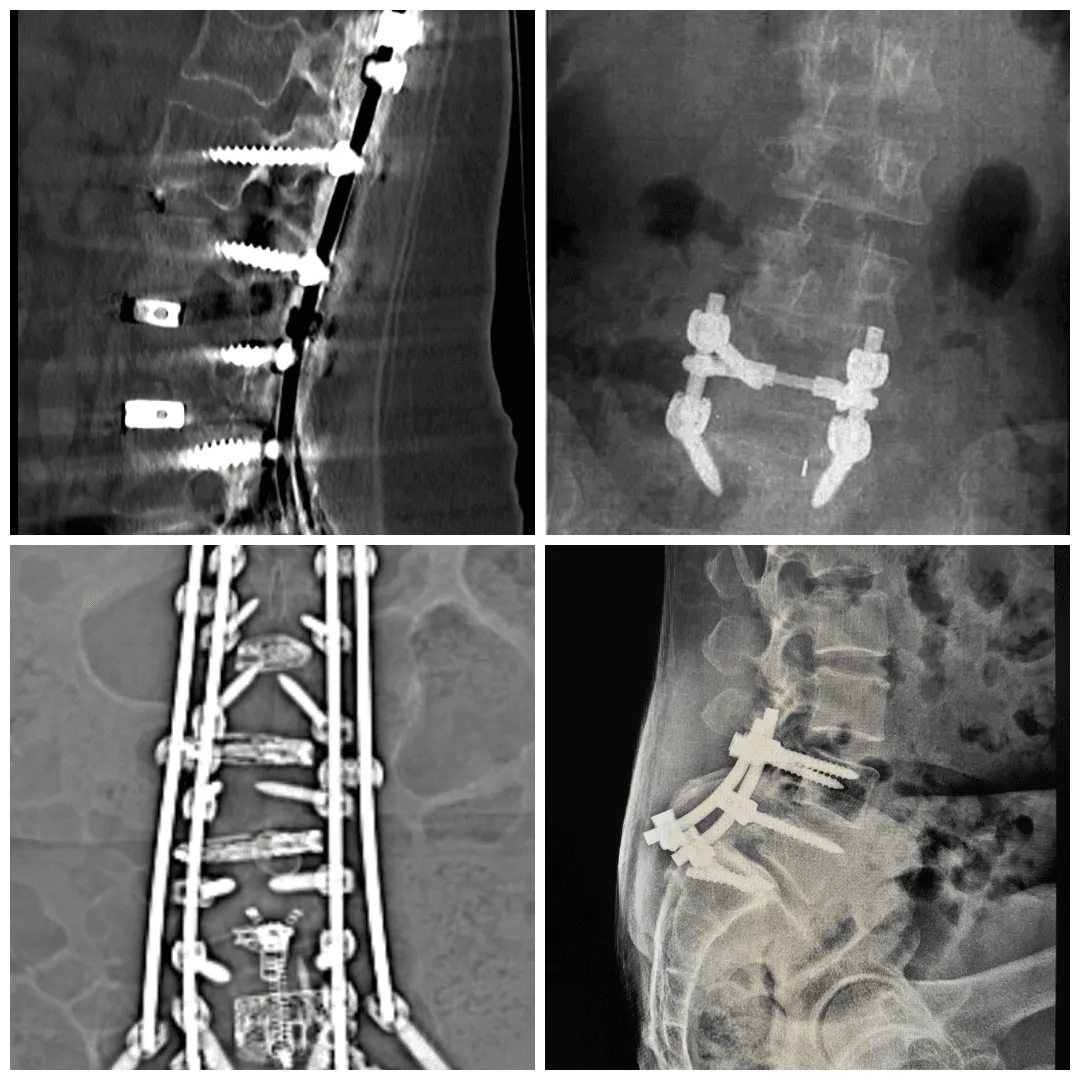

Spinal fusion surgery is a traditional approach to treating conditions such as herniated discs, sciatica, degenerative disc disease, and spinal stenosis. During this procedure, two or more vertebrae are permanently joined using metal hardware (screws, rods, and cages) along with bone grafts. The goal is to eliminate motion at a painful segment of the spine.

During a spinal fusion procedure, surgeons access the spine through various approaches. They remove the damaged disc material, prepare the vertebral surfaces, place bone graft material between the vertebrae, and secure everything with metal hardware to hold the vertebrae in position while the bone graft heals and forms a solid bony bridge.

The fusion process takes approximately 3–6 months, during which the vertebrae gradually grow together. Once complete, these vertebrae function as a single, solid bone segment, permanently eliminating motion at that level.

Hardware Complications

Screws, rods, and cages can fail, shift, loosen, or even cause allergic reactions in some patients. Hardware complications include:

Screw loosening or pullout: The screws anchoring the construct can loosen from the bone, causing pain and instability

Rod fracture: The metal rods connecting the screws can break under stress, particularly in long fusions

Cage subsidence: The interbody cages placed between vertebrae can sink into the vertebral body, losing height and potentially compressing nerves

Hardware prominence: Screws or rods can become prominent under the skin, causing discomfort and sometimes requiring removal

Allergic reactions: Though rare, some patients develop metal sensitivity or allergic reactions to titanium or other hardware materials

A 2023 study examining the influence of screw positioning found that proper hardware placement is critical for preventing cage subsidence and maintaining fusion integrity.

Additional surgeries may be needed to correct hardware issues, revise failed fusions, or address adjacent segment problems.